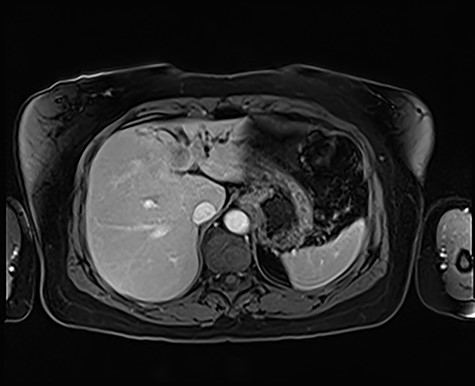

A 54-year-old female, of Philippines descent, presented to our department following the incidental discovery of a 23 × 20 mm ill-defined mass within segment II/III of the liver during ultrasound workup for mildly deranged liver function tests. She had no symptoms from the lesion, and she reported no significant past medical history. A pre- and post-contrast multiphase helical computed tomography identified a 26 × 25 mm ill-defined region of hypodensity, with a small focus of central calcification, within segments II and III of the liver (Fig. 1). The lesion was causing biliary obstruction indicated by dilatation of the intrahepatic biliary ducts within the entire left lobe of the liver and appeared to be in continuity with the left hepatic duct. Magnetic resonance imaging of the liver identified an irregular enhancing mass within segment IV that had a central area of non-enhancing low signal intensity (Fig. 2). As a part of the patient’s workup for presumed malignancy, an upper and lower endoscopy, bilateral mammogram and ultrasound assessment of the breasts were all found to be normal. A biopsy was not able to be obtained due to the proximity of the lesion to the porta hepatis.

magnetic resonance imaging, T2-weighted image demonstrating an irregular, enhancing mass within segment IV that has a central area of non-enhancing low signal intensity